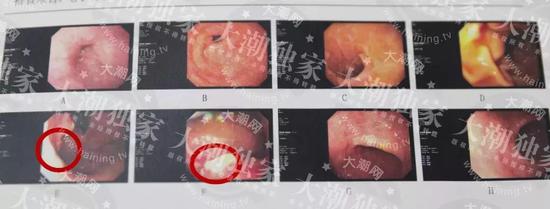

△紅圈圈出位置為癌變部位當(dāng)然啦,最最重要的就是養(yǎng)成良好的生活習(xí)慣,好好保護自己的胃,飲食要規(guī)律、不要狼吞虎咽,多吃些蔬菜水果,減少食鹽的攝入。也不要過度勞累,造成自己的精神緊張。